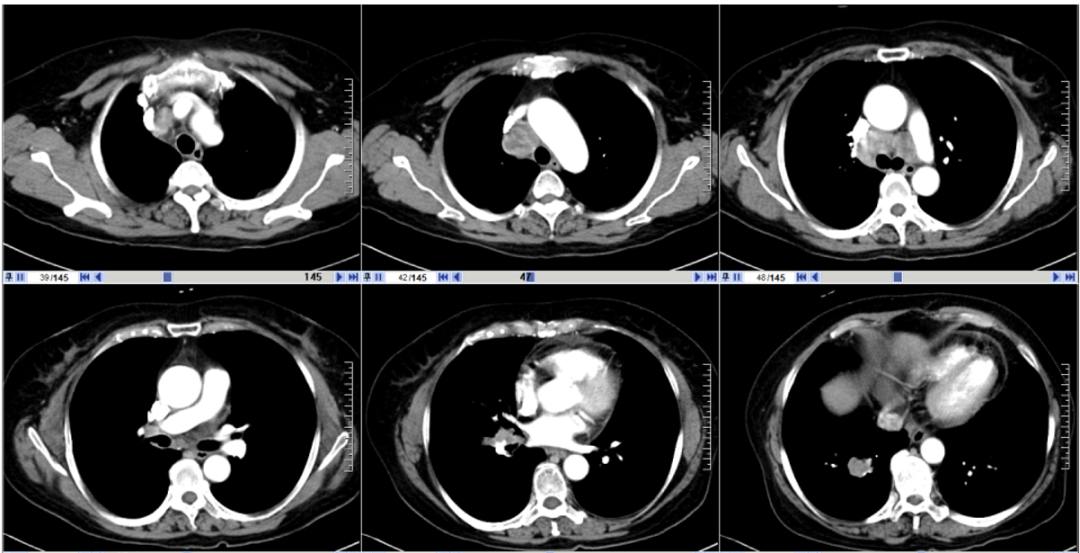

2021年1月14日行胸腹部增强CT。

图1. 2021年1月14日胸腹部CT

图像